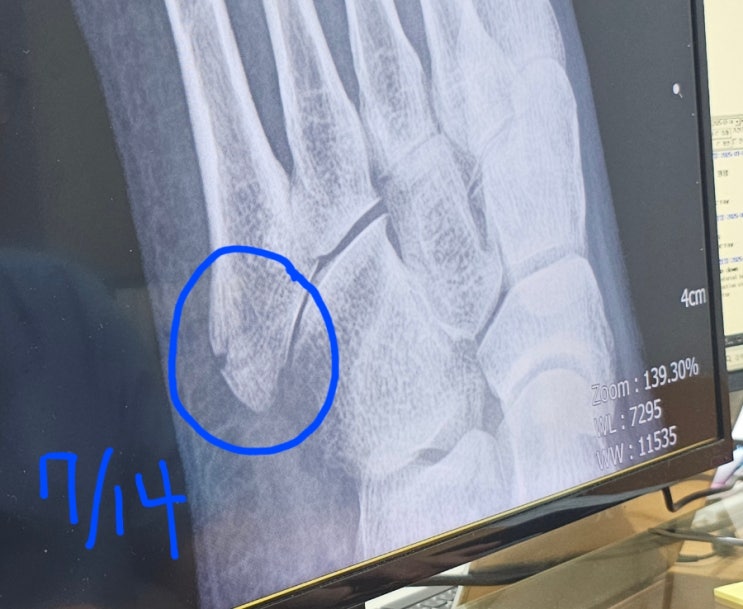

발등골절 제5중족골 기저부골절 비수술 4주차 5주차

발등골절 제5중족골 기저부골절 비수술 3주차 꽉차고 4주차 시작(7.14)일인 월요일에 병원가서 사진 찍었습...

발등골절 제 5중족골 기저부골절 비수술 3주차

발등골절 제5중족골 기저부 골절후 3주차에 접어 들었습니다. 일주일에 한번씩 월요일마다 병원에 가고 있...